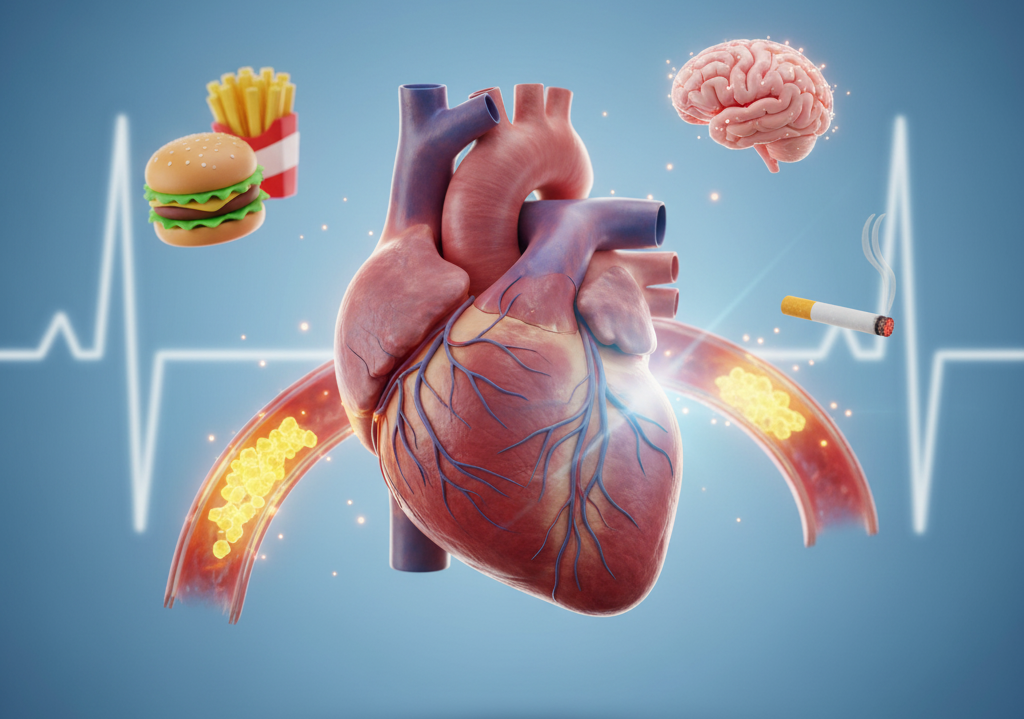

Heart Disease: Types, Causes, Symptoms, and How to Prevent It

It includes conditions like heart failure, arrhythmias, and coronary artery disease that affect the structure…

Heart Attack Can Happen During the Exercise Causes & Risks

While the exercise is essential for maintaining heart health, some of the factors may trigger…